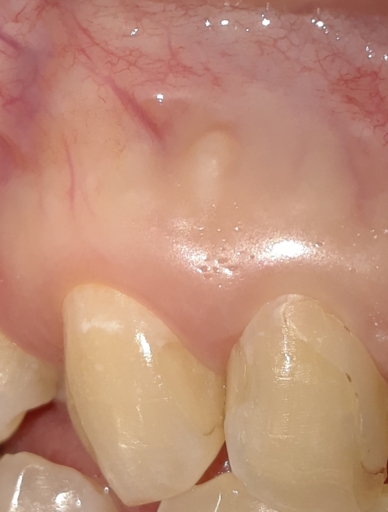

Is it possible to have a tooth thats infected for "a long time" but not need to be treated with an antibiotic? This dentist claims my friend needs a root canal and a crown(she's on medicaid) and medicaid doesn't cover either. they said she could have it pulled, but then it would be more expensive in the long run(probably because of the partial expense-pontic and retainer charge, I am guessing)... But they also said she could just leave it and do nothing for now.As far as I know people still die from tooth infections getting out of control and going to the heart and brain. it seems reckless or at the other end like they are full of it. More details -> my girlfriend is 35, and thats who I am asking for. she feels pain when drinking or eating cold foods. she has a big filling there already. which I figured there must be a spot there where the filling is not sealed properly.

Anytime anyone has a infection in the mouth from a tooth, usually needs antibiotic. As you mentioned that your girlfriend is on medicaid, which they do not cover dental. I suggest that she has the tooth removed and later when you could afford a partial denture you can do it. You did not mention which tooth, so its difficult to determine what to do. But she should be on anitbiotic. As the infection is not good for our body to fight. If you leave it alone, it will come back. As far as what the dentist said about a root canal and then a crown later. The nerve in that tooth is dying or died and that causes infection if not treated.